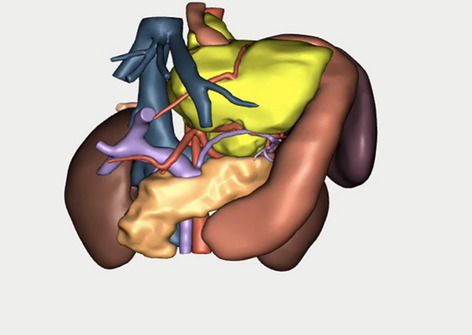

Methods: 3D virtual models were created through manual segmentation of CT and MRI scans obtained according to protocols routinely used in colorectal cancer staging. No extra patient time or preparation were needed. CT and MRI images were analysed by Gastrointestinal Radiologist to delineate the tumour and provide the cancer staging. Manual segmentation was then performed in 3D Slicer, an open-source, free software used for creation of three-dimensional anatomical models. Additional post-processing was applied in MeshLab or Blender.

Results: Ten 3D models depicting tumour deposits in colorectal cancer were created. Models of right- and left-sided bowel cancer with tumour deposits were derived from CT scans, while those of rectal cancer—from MRI scans. 3D models depicted bowel with the tumour and tumour deposits, relevant vasculature and lymph nodes, as well as surrounding structures as required. Models can be manipulated to allow for most comprehensible inspection of different anatomical structures and relationships. The transparency of each structure can be changed. The morphological appearance of tumour deposits and their relation to vessels can be readily appreciated. The morphological differences between the tumour deposits and lymph nodes, both benign and metastatic, can also be evaluated.